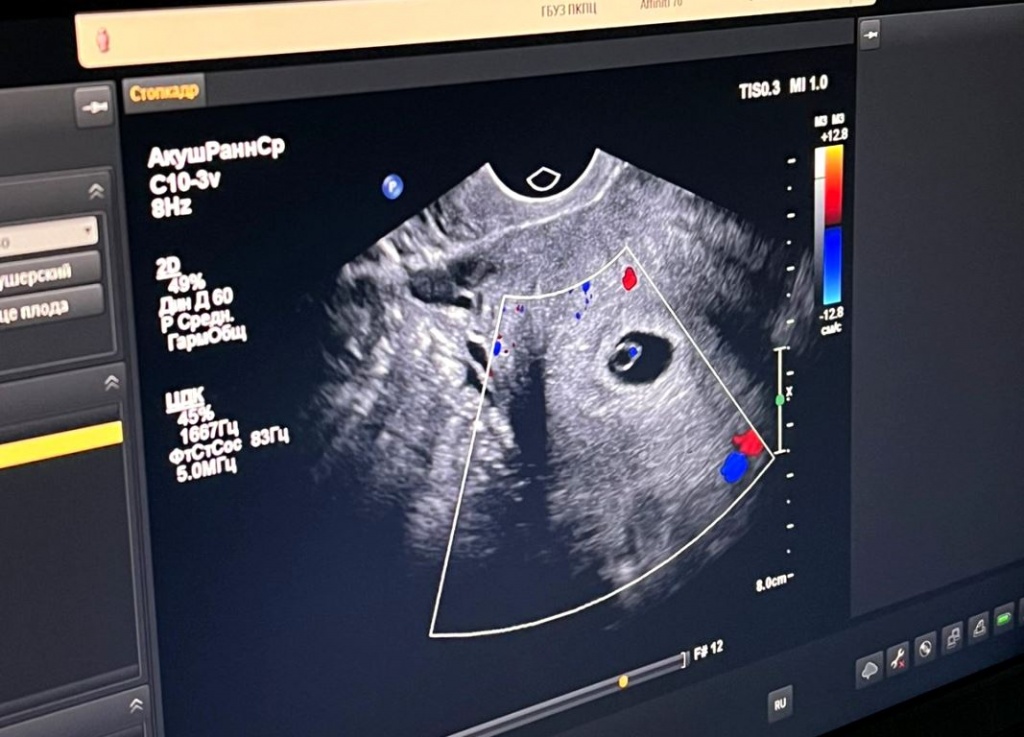

С каждым днём все больше приморских семей исполняют свою главную мечту – стать родителями. Только с начала года врачи Приморского краевого перинатального центра помогли исполнить заветное желание 160 приморским семьям, проведя бесплатные процедуры ЭКО.Отделение ЭКО Приморского краевого перинатального центра распахнуло свои двери весной прошлого года, и уже в канун Нового года первые семьи, прошедшие процедуру, празднование рождение своих малышей. Сегодня здесь с каждым днём всё больше и больше семей слышат долгожданную фразу врачей «Поздравляем! Вы беременны».